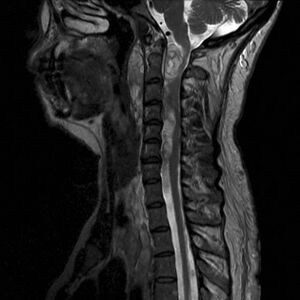

- MR – primary choice, especially axial and sagittal T1 and T2 images. In practice, DTI (diffusion tensor imaging) and FT (fiber tractography) are already commonly used for more detailed imaging of white matter pathways (their displacements, compression, etc.) due to tumor location. [5][6][7].

- Diagnostika: DTI, MRI